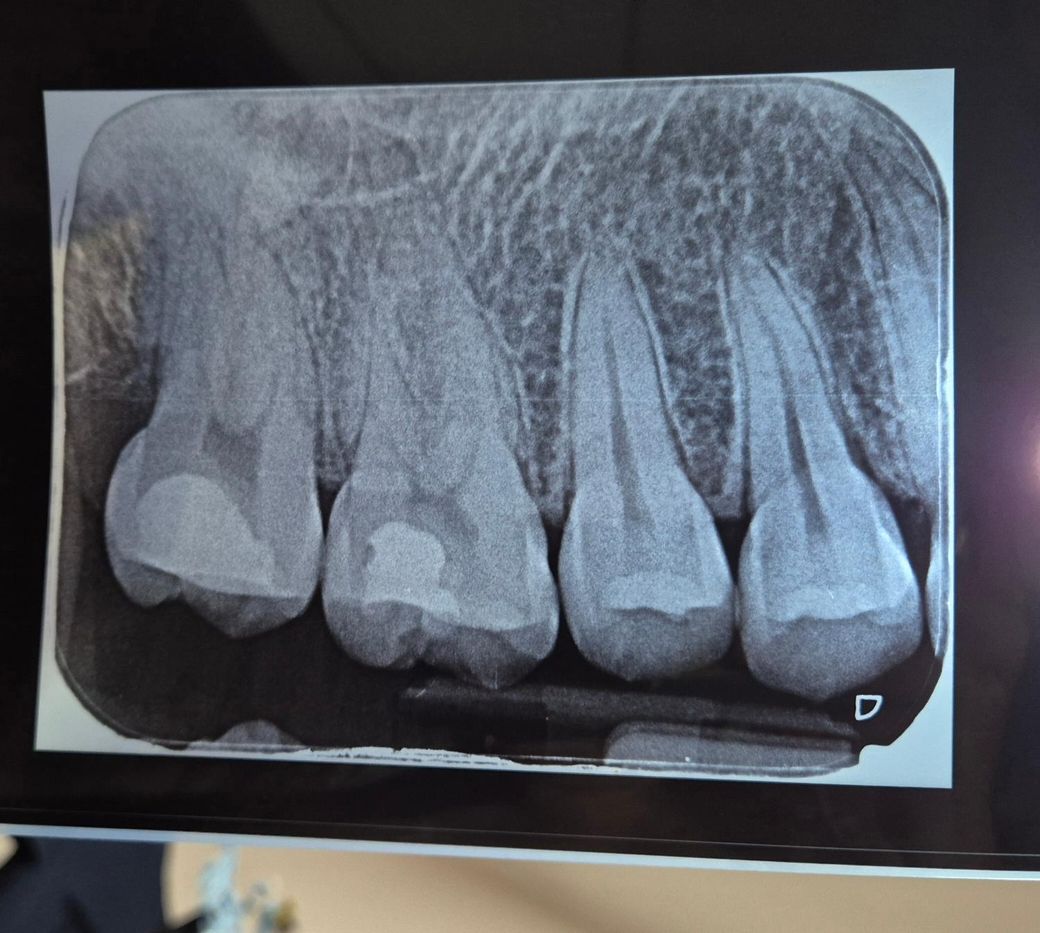

위 오른쪽 끝 어금니가 너무 아파요ㅠㅠ

지금 콜롬비아에 있는데, 일주일 전부터 오른쪽 위 끝 어금니가 아파요. 통증때문에 잠도 잘 못자고.. 일단 통증을 참기 힘들때 이지엔6 먹고있어요.

어제부터는 음식물을 씹어도 아프네요ㅠㅠ 사진도 찍고 했는데, 사랑니도 아니고, 충치도 아니라고해요ㅠㅠ

끝에서 두번째 치아에는 충치가 있는데 끝에는 없다고..

일단 몇년 전에 충치 치료하고 떼운게 있는데 그게 높아서 밑에 어금니랑 물리면서 충격이 간것 같다고.. 낮게 깎아줬어요!!

혹시 사진 보시고 이상이 있는지 문의 드립니다!!

엑스레이상 뿌리끝 염증이 있거나 그런것은 아니나 애초에 충치가 아주 깊었습니다 치수염이 유발된 상태일 수 있습니다

오른쪽 위 맨끝어금니와 그 앞 어금니 모두 기존 수복물이 꽤 깊어 보입니다. 본래에도 충치가 심해서 치료를 했던 것 같고, 자발통 때문에 진통제를 복용해야 할 정도라면 비가역성 치수염이나 치아의 균열을 의심할 수 있습니다. 치아신경검사가 필요하고 경우에 따라 신경치료가 필요할 수 있습니다.